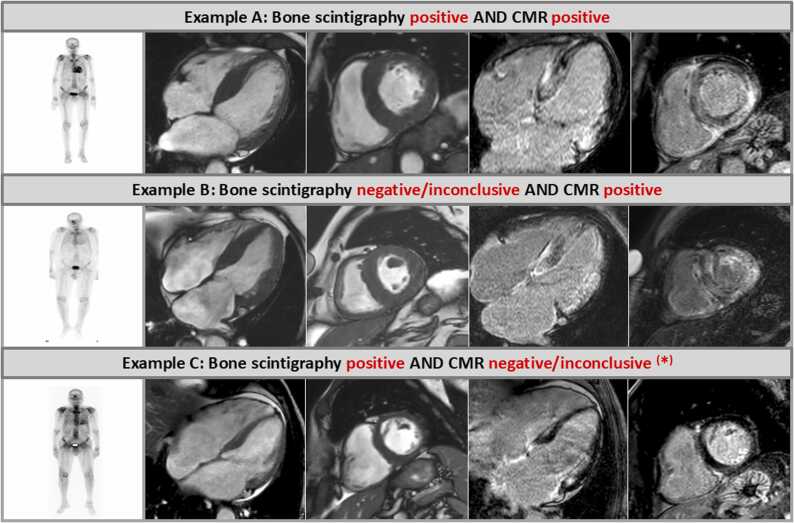

Results: One hundred twenty three patients in whom the final diagnosis was obtained either non-invasively based on combined findings from bone scintigraphy and monoclonal protein studies or invasively based on additional EMB findings were included. A positive CMR result indicating the presence of CA was found in 121 patients-suggesting a CMR sensitivity of 98.4% for the diagnosis of any CA. Bone scintigraphy identified 18 patients with low to moderate uptake (Perugini score = 0-1) and 105 patients with high uptake (Perugini score ≥2)-resulting in a sensitivity for bone scintigraphy of 85.4% for the diagnosis of any CA. There was an agreement ("diagnostic match") between CMR and bone scintigraphy results in 103 patients (84%) of the total study cohort, while a discrepancy ("diagnostic mismatch") was observed in 20 patients (16%). In 18 out of these 20 diagnostic mismatch cases, CMR correctly diagnosed the presence of CA despite a negative or inconclusive result on bone scintigraphy (8 with AL-CM, 8 with ATTR-CM, and 2 with EMB-proven but unspecified CA).

Conclusion: CMR shows a substantially higher diagnostic yield for the diagnosis of CA compared to bone scintigraphy, if a real-world cohort of patients comprising different subtypes of CA is looked at, since CMR does not only detect ATTR-CM but also depicts other CA subtypes such as AL. In case of a clear-cut positive CMR result unequivocally indicative of CA, there is no incremental diagnostic value of an additionally performed bone scintigraphy.